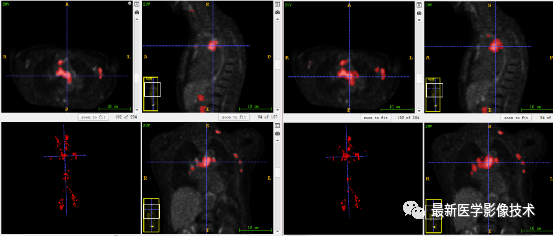

7、验证集分割结果:输入整个图像通过滑窗叠加预测结果,左图是金标准,右图是预测结果